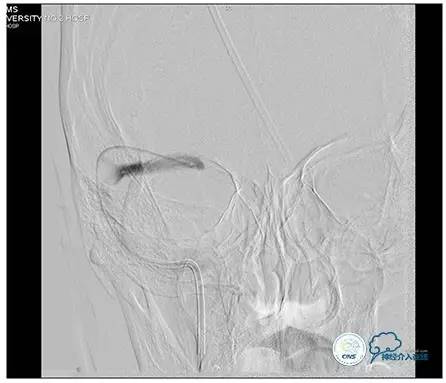

术中造影

5ml/s,总量8ml,压力100~150

手术方案

1、6mm×20mmAviator球囊(Cordis)分段对狭窄部位进行扩张。

2、植入7mm×40mmPrecise自膨支架。

术后造影

术毕远近端压力差为:0